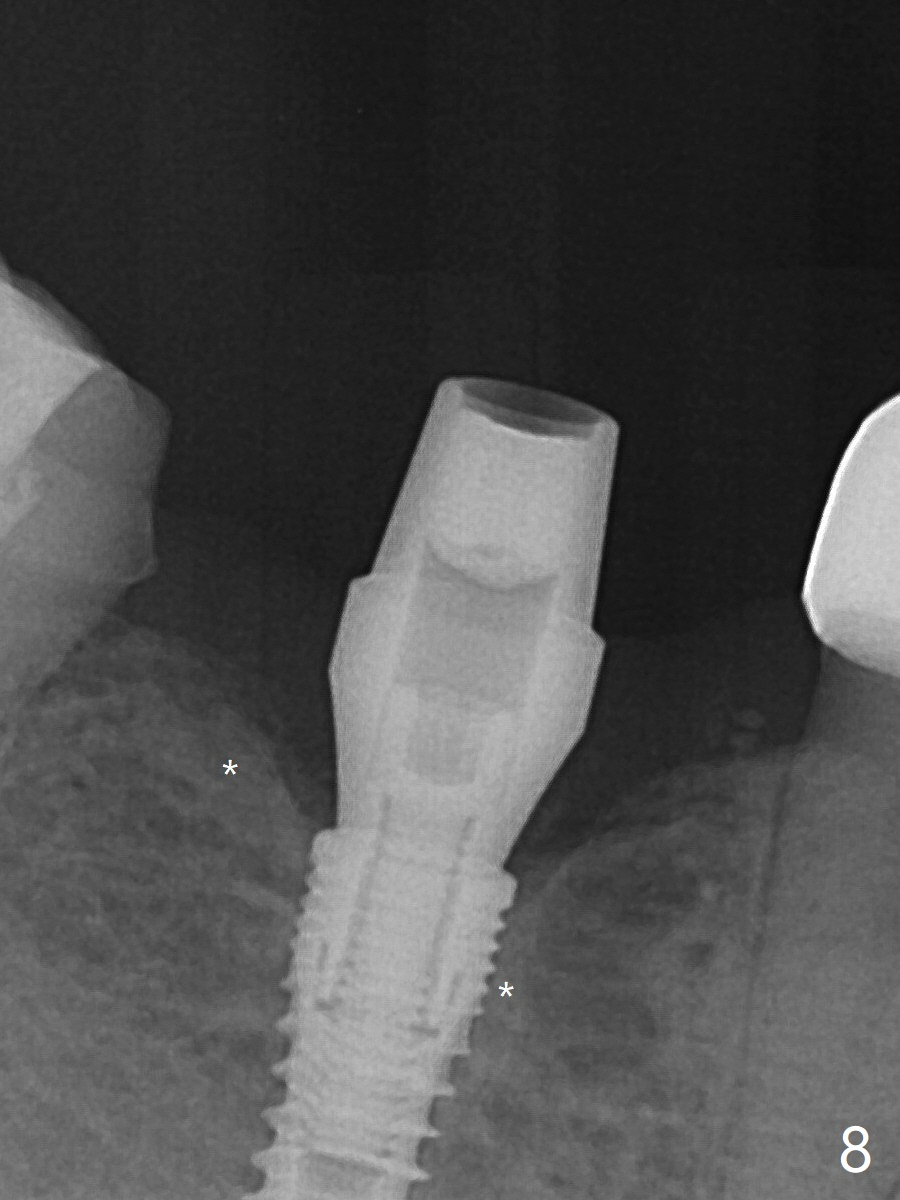

There appears dense bone formation 3 months postop (Fig.8 *).